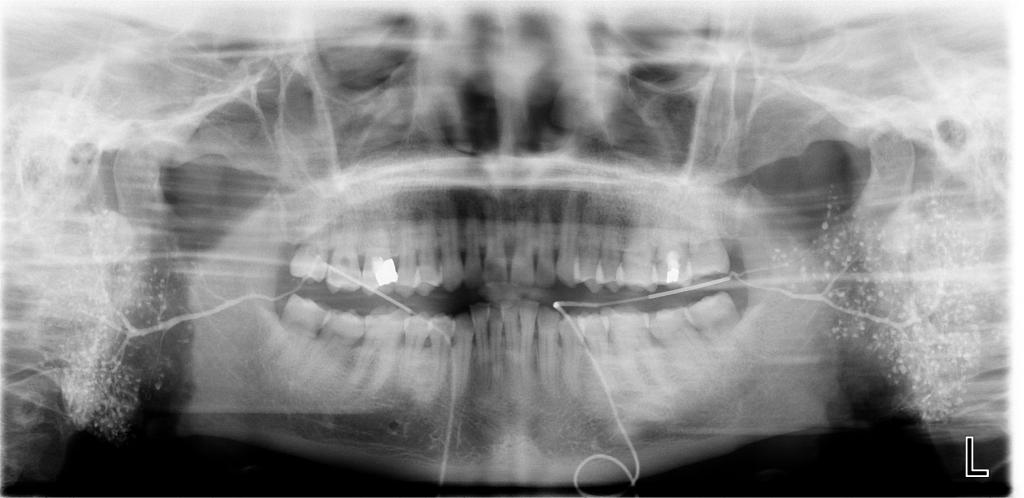

数字化口腔曲面体层片

诊断范围涉及牙体牙髓病、牙周病、阻生牙/多生牙定位、种植牙术前CT评估分析、颞下颌关节CT诊断分析、,颌骨及涎腺疾病、颌面发育畸形、正畸治疗辅助诊断等大部分颌面部疾病,为临床医疗提供强有力的支持。